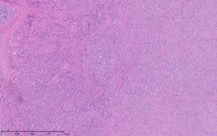

As part of the patient’s treatment, the thoracic surgery team performed a right middle and lower lobectomy. A 4-cm mass in the right bronchus intermedius without invasion into the lung parenchyma was revealed, and pathology confirmed the diagnosis of leiomyosarcoma. The sections of pulmonary tissue from the right middle and lower lobectomy showed a spindle cell tumor most consistent with leiomyosarcoma (Figure 3a-d). Most of the tumor was low grade, with some foci showing high-grade nuclear atypia and increased mitotic activity. Despite these rare mitotic figures, there was no evidence of necrosis. Following surgery, chemotherapy was planned for the patient. However, the patient’s postoperative course was complicated by persistent hypoxic respiratory failure, hypovolemic and hemorrhagic shock, and acute kidney injury. Her respiratory status continued to decline, and she went into cardiac arrest with pulseless electrical activity. She was resuscitated; however, her shock and respiratory failure worsened despite aggressive therapy. Her family chose to transition her to comfort care, and the patient died.

The patient’s malignancy followed the typical behavior of endobronchial leiomyosarcoma. These tumors are expected to expand locally, although there was no evidence that her tumors had yet reached this stage of invasion. After lobectomy, surgical pathology of the mass obstructing the bronchus intermedius demonstrated that the tumor had not invaded the visceral pleura, nor were there positive margins at the bronchial, vascular, or parenchymal margins. The tumor was 1 cm from the closest margin. Also in alignment with the diagnosis of a low-grade leiomyosarcoma, there was no evidence of malignant spread to any of the 4 lymph nodes histologically examined, and Ki-67 staining highlighted less than 5% of cell nuclei in the right lung mass and less than 1% of cell nuclei in the left lung mass. Her tumor staging was pT3 pN0.